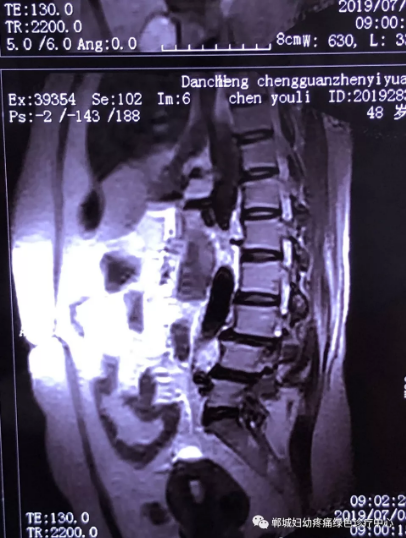

2年前,双楼乡的陈女士不小心摔了一跤后出现腰痛,当时到药店买了膏药来贴,疼痛减轻了一些,但是从此以后反反复复出现腰痛。到处进行治疗,不见好转,最近腰痛加重了,痛得受不了,出现行走后甚至持续的双下肢后侧或后外侧放射性的疼痛麻木、间歇性跛行等症状。陈女士赶忙去医院治疗,做了磁共振检查后确诊为腰椎滑脱、腰椎反弓。医生都告诉她需要手术治疗。随后她又带着片子咨询了好几家医院,结果都是一样,她已经做好了手术的打算。

治疗前

不经意间听到有人说医院疼痛科可以不吃药不打针,用无痛苦、无创伤的方法治疗腰痛。陈女士就抱着试试看的心理来到了郸城县妇幼保健院疼痛科,疼痛科时庆祥主任详细了解病情,结合腰椎磁共振及体征后告诉陈女士她不用手术,通过腰椎脊柱定位周期减压牵引系统(外星舱)也能解决腰痛、腰椎滑脱、腰椎反弓这些问题。陈女士未曾想到经过十五天的治疗后腰部及下肢放射性疼痛症状基本消失。陈女士感到十分激动与感谢,就在当地卫生院做了一个腰椎正侧位x片和之前的片子作对比,发现腰椎滑脱明显改善。她说道:感谢郸城县妇幼保健院疼痛科的所有医护人员、感谢外星舱脊柱减压治好了我的腰痛,也感谢告诉我来这里的人,她的一句话,让我省了好几万元的手术费!